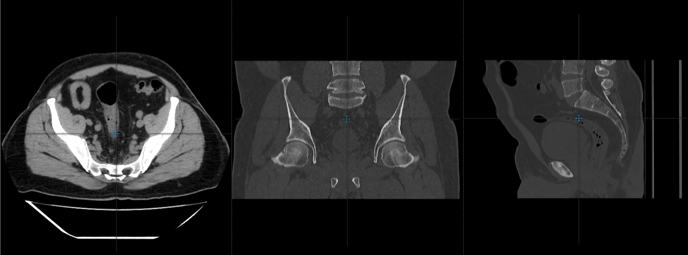

¿Cómo visualizar el mismo punto anatómico en diferentes planos en el visor web?

Te mostraremos la herramienta que permite situar un punto anatómico en todos planos

1. Selecciona la herramienta de triangulación

que encuentras en la parte superior del visor.

2. La cruz de color azul te permitirá con un clic izquierdo sostenido desplazar el mouse e ir visualizando el mismo punto anatómico o nivel de corte en los tres planos.